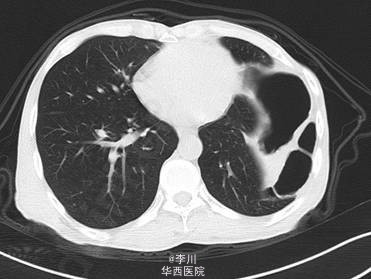

患者男,49岁9月,因“ 全腹胀痛14天,加重伴呕吐4天”入院。患者14天前在进食“甜酒”后出现腹部胀痛,逐渐扩大到整个腹部,伴恶心干呕,不伴寒战发热、腹泻、晕厥,无心悸、气促、发绀。外院诊断“肠梗阻”,予以石蜡油灌肠及输液治疗后缓解。4天前患者在进食后出现同前症状,遂于我院就诊。

既往患者1+年前因摔跤撞伤腹部,于贵阳医学院行“脾切除+膈疝修补术”。查体左肺呼吸音减弱,可问及异常肠鸣音。CT提示:左侧膈面上抬、局部膈肌软组织似不连续,可见胃及部分肠管上移,膈疝?

在全麻下经左胸膈疝修补、胸膜粘连烙断、胸腔闭式引流术。术中发现:左膈肌外侧缺损约15cm×12cm大小,腹腔内网膜、胃及横结肠等组织疝入胸腔。网膜、胃、结肠组织与膈肌、胸壁片状粘连。左侧肺与胸壁广泛粘连。术后予抗炎、化痰、对症等治疗后好转。